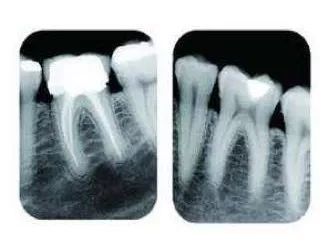

例如當牙齒有好深嘅齲壞時,憑口內檢查嚟話唔到齲洞有幾深、離牙神經有幾遠同埋有冇同牙根發炎相關嘅資訊。

由於牙齒下部隱藏喺牙床骨入面,口腔醫生要瞭解牙齒嘅整體情況就需要拍攝全景片;而要了解各個牙根同埋周圍嘅變化,則選擇拍攝小牙片。

所以,影牙片係一種幫助牙科醫生進行診斷、治療、療效評估嘅重要手段,治療前用於發現病變程度、範圍;治療中用於引導治療、確定治療範圍和深度;治療後用於觀察療效。